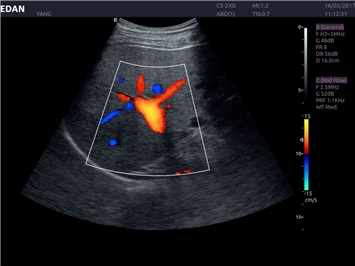

• Кардиологических исследований

Трехмерная реконструкция ЦДК:

Да

Тканевой допплер:

Color 3D: